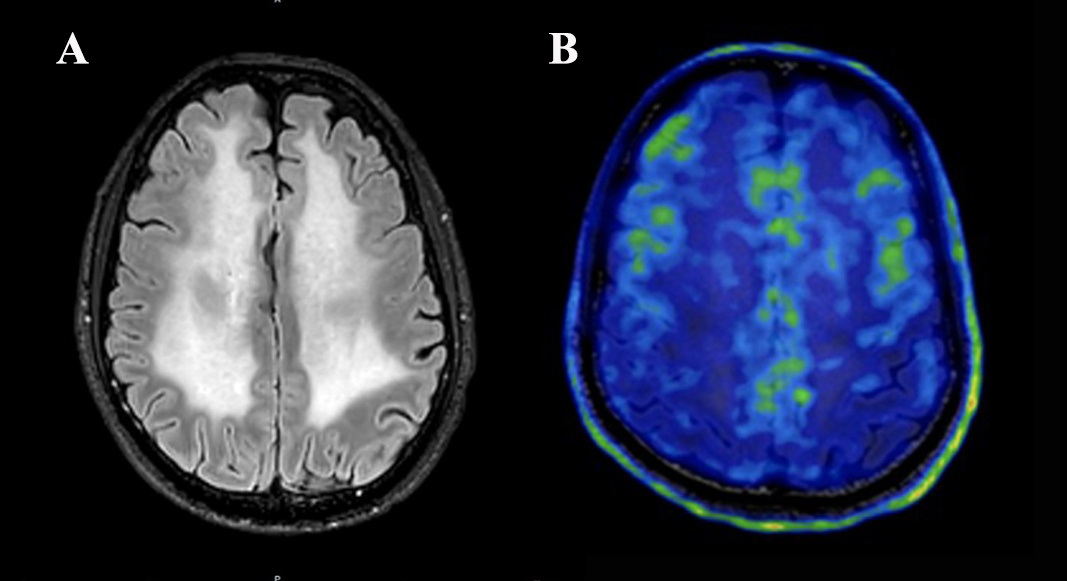

图1 治疗前,传统的核磁发现李先生大脑白质区域几乎完全变“白”,瑞金医院进一步采用全球先进的“炎症核磁”发现了“端倪”,李先生脑内“炎症活跃”(绿色区域表示炎症活跃)。

结果不出陈晟主任所料,该患者全脑区均见到炎症的异常增高,就像大脑里燃起了看不见的“鬼火”。那么导致“着火”的原因是什么呢?进一步的检查发现李先生血清和脑脊液中存在一种罕见的抗体:GFAP抗体。随即,一种罕见的疾病浮现出来了,GFAP抗体相关脑炎。